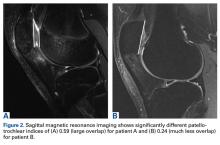

The PTI is correlated with tibia-based measures of height, but the correlation is not perfect. Lower degrees of overlap between the patella and the trochlea (PTI <0.15) and significant functional patella alta may warrant adding TTDO in cases of borderline CDI (1.2-1.4). Figures 1A, 1B and 2A, 2B show the imaging of 2 patients with relatively similar patellar height (assessed with CDI) but quite different degrees of overlap between the patella and trochlea. The patient with less overlap is more likely to have delayed patellar engagement and symptomatic patella alta and thus may be a poorer candidate for isolated MPFL reconstruction. For additional information, please refer to the work by Roland Biedert, MD, who has proposed trochlear lengthening in these situations.13Physical examination (even in the era of advance imaging) continues to provide useful insight into whether to add TTDO. One physical examination test that can help in understanding patellar-